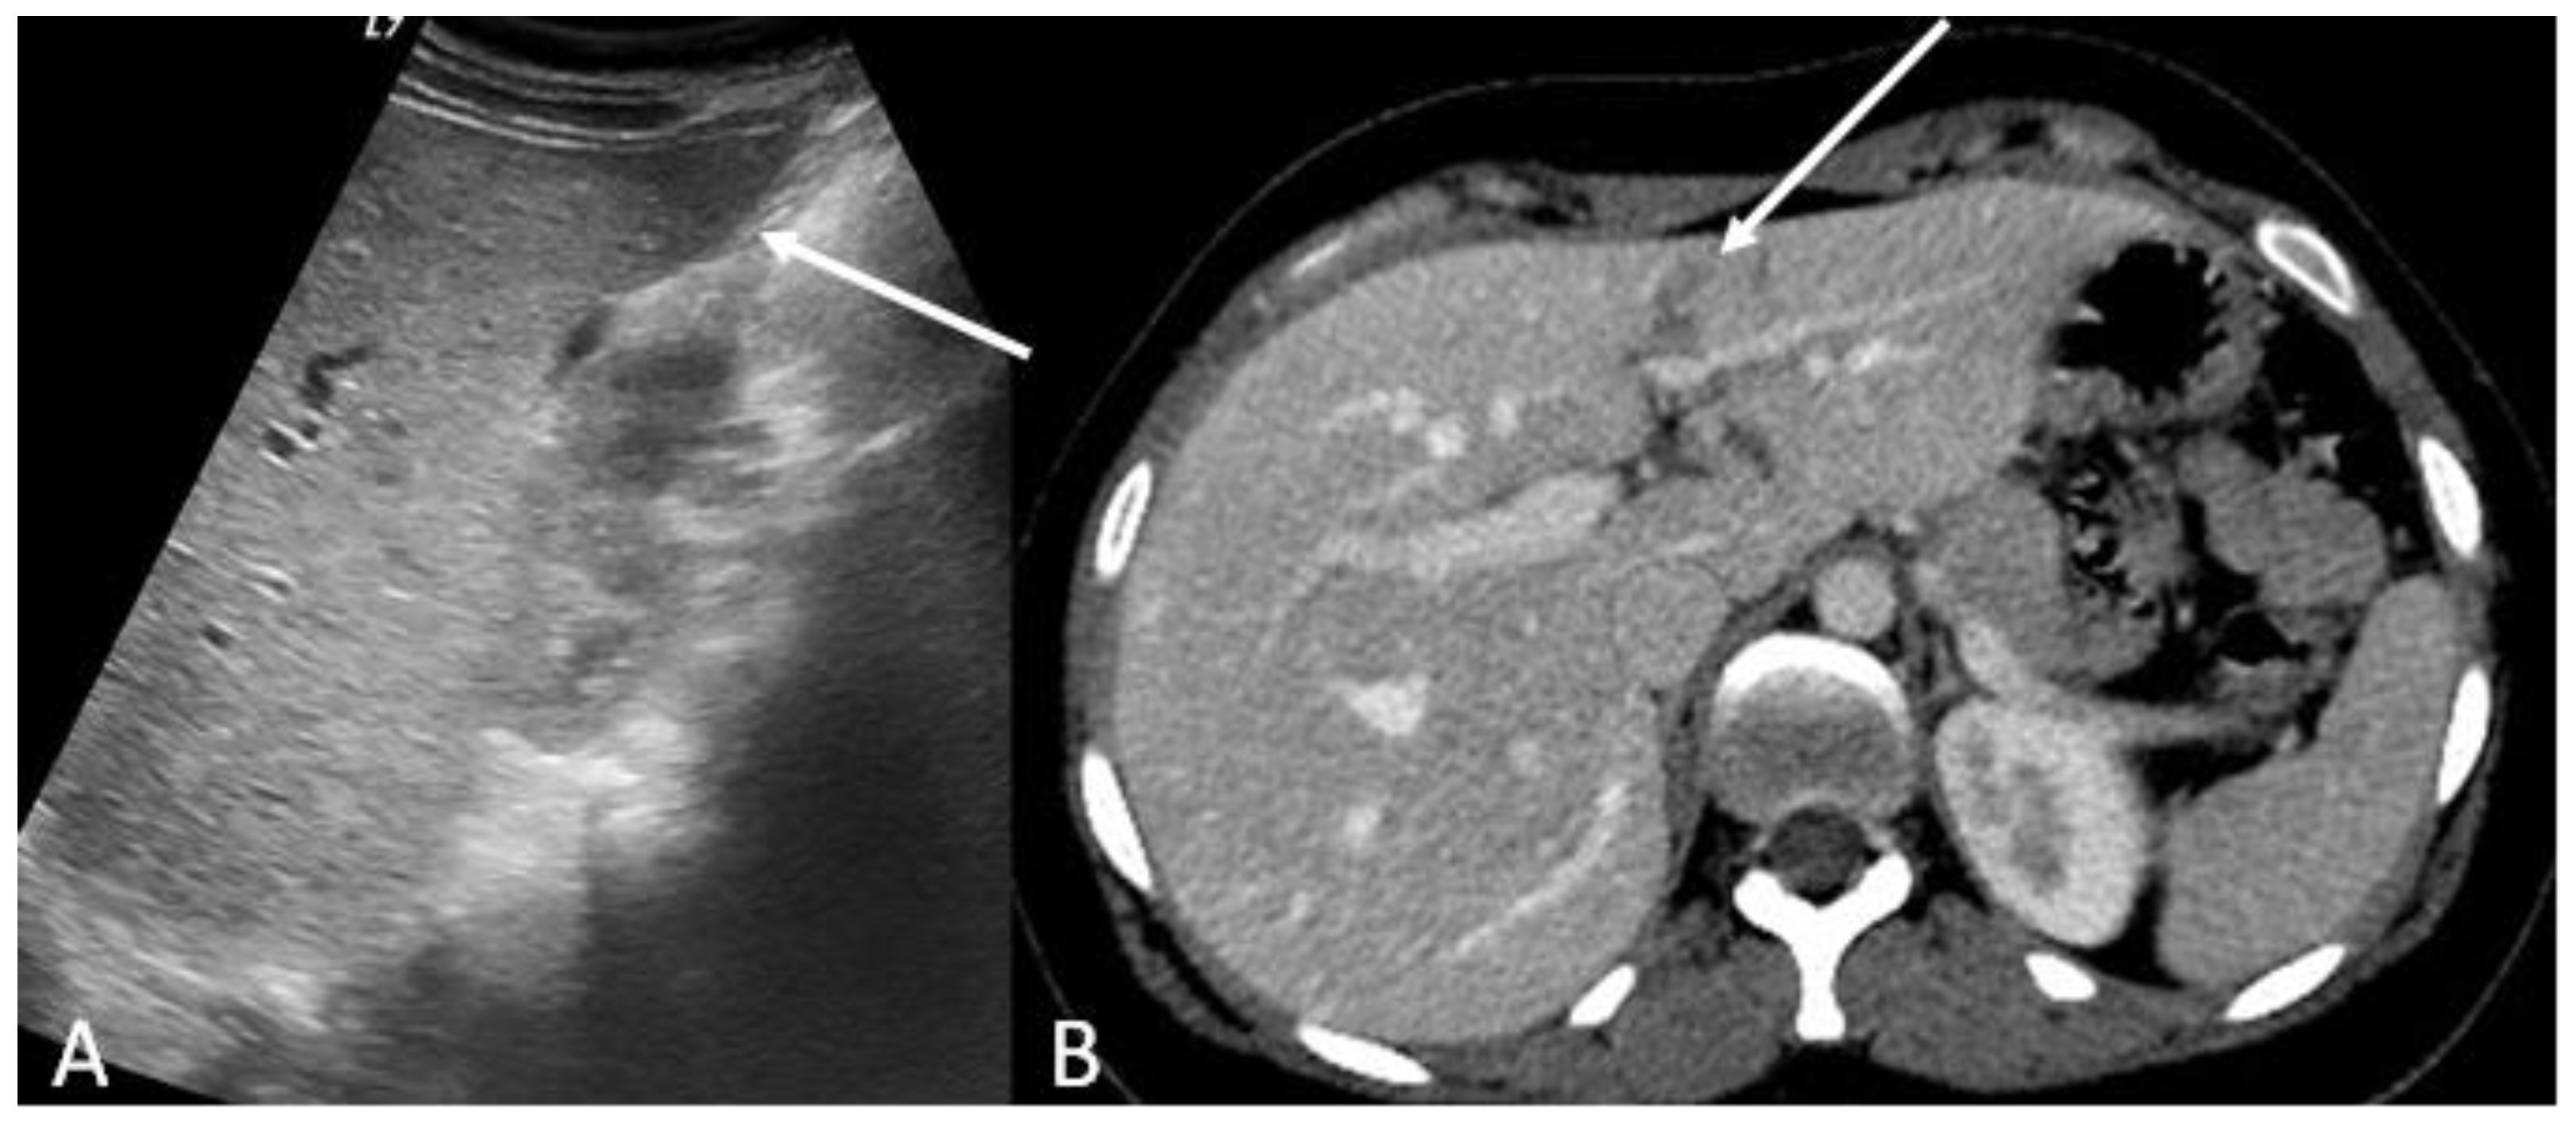

- Iacobellis, F.; Laccetti, E.; Tamburrini, S.; Altiero, M.; Iaselli, F.; Di Serafino, M.; Gagliardi, N.; Danzi, R.; Rengo, A.; Romano, L.; et al. Role of multidetector computed tomography in the assessment of pancreatic injuries after blunt trauma: A multicenter experience. Gland Surg. 2019, 8, 184–196. [Google Scholar] [CrossRef]

- Søreide, K.; Weiser, T.G.; Parks, R.W. Clinical update on management of pancreatic trauma. HPB 2018, 20, 1099–1108. [Google Scholar] [CrossRef]

- Soto, J.A.; Anderson, S. Multidetector CT of Blunt Abdominal Trauma. Radiology 2012, 265, 678–693. [Google Scholar] [CrossRef]

- Hassan, R.; Aziz, A.A. Computed Tomography (CT) Imaging of Injuries from Blunt Abdominal Trauma: A Pictorial Essay. Malays. J. Med. Sci. 2010, 17, 29–39. [Google Scholar]